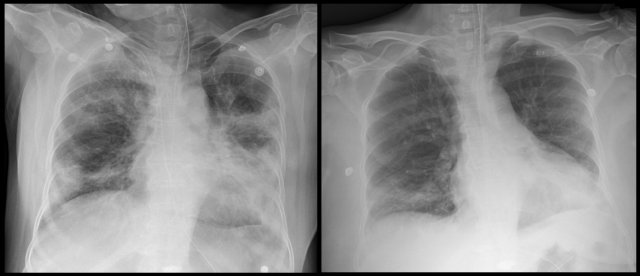

스테로이드 치료까지 병행한 결과 뿌옇게 보이던 김 씨의 폐가 나아졌고 이후 완치 판정을 받았습니다.

鎖骨と胸骨の接続位置が、高いような気がする。んで、肋骨間の間隔が、なんか、開きすぎてるような気もする。あの間隔で肋骨が配列されていたら、12番目の肋骨の先端は、骨盤に突き刺さるのでは?。